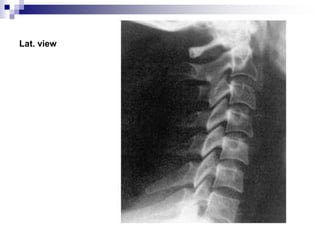

 X-ray

Standard radiographic series comprises AP,

lateral and open-mouth views.

All seven vertebrae should be visible in lat.

View.

Alignment of cervical lordotic curve.

Assess the disc spaces.

Lat. view